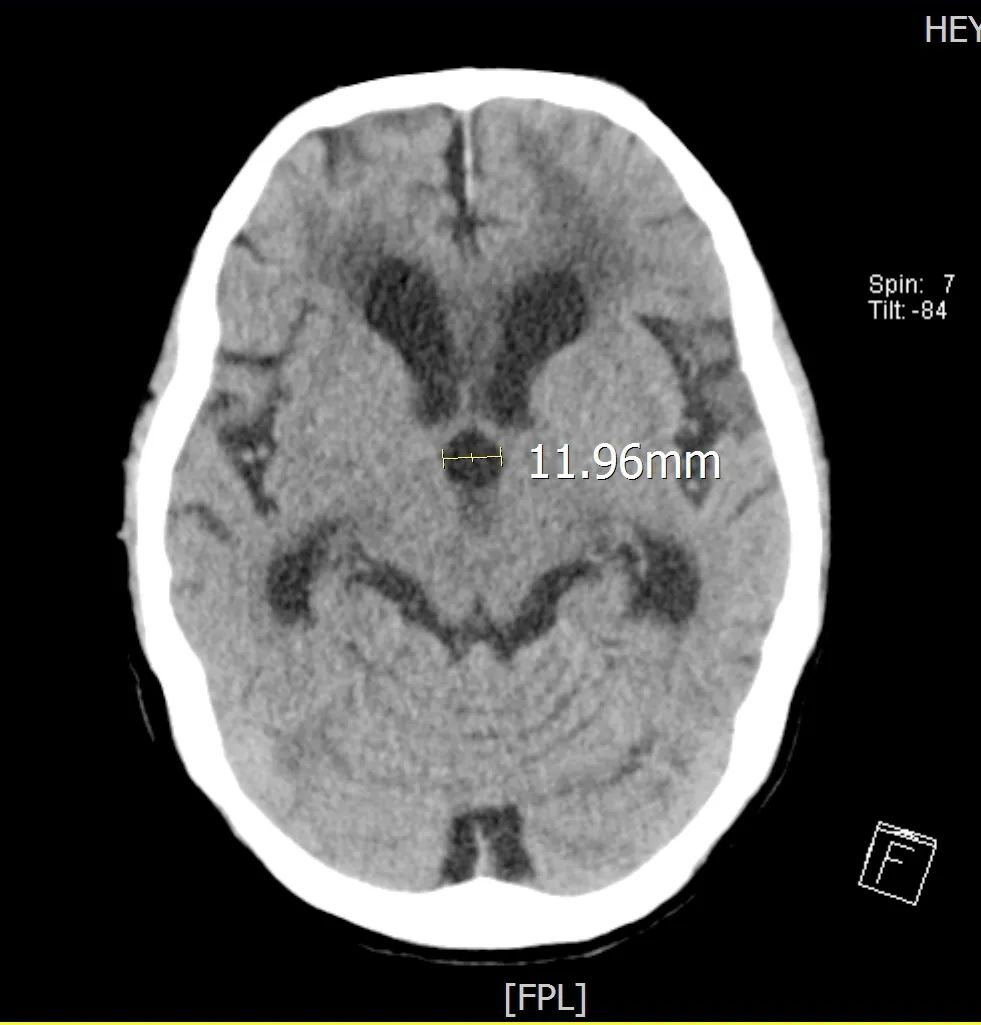

患者入院后我院专家团队为患者做进一步检查:患者神志清,言语障碍,认知能力明显下降,记忆力、计算力检查不能配合,双上肢肌力4级,右下肢肌力3+级,左下肢肌力3﹣级,双下肢肌张力高,无法在床上坐稳及完成站立动作。10月24日我院颅脑CT:左侧额颞叶低密度影,考虑脑挫伤后遗症改变;脑积水并间质性脑水肿,左侧顶骨骨折,矢状缝后部缝离骨折。

▲术前CT 三脑室直径>1cm